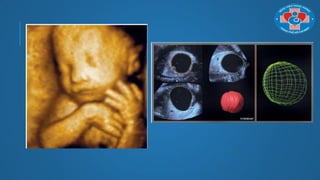

ĐO THỂ TÍCH (VOCAL – VIRTUAL ORGAN

COMPUTER AIDED ANALYSIS)

Đo thể tích nội mạc để tiên lƣợng K nội mạc

Đo thể tích phổi còn lại để tiên lƣợng trên thai nhi có thoát vị hoành

Đo thể tích đùi thai nhi để tiên lƣợng ƣớc lƣợng cân nặng

ĐO THỂ TÍCH(VOCAL – VIRTUAL ORGAN COMPUTER AIDED ANALYSIS) Đo thể tích nội mạc để tiên lƣợng K nội mạc

ĐO THỂ TÍCH(VOCAL – VIRTUAL ORGAN COMPUTER AIDED ANALYSIS) Đo thể tích phổi còn lại để tiên lƣợng trên thai nhi có thoát vị hoành

ĐO THỂ TÍCH(VOCAL – VIRTUAL ORGAN COMPUTER AIDED ANALYSIS) Đo thể tích đùi thai nhi để tiên lƣợng ƣớc lƣợng cân nặng